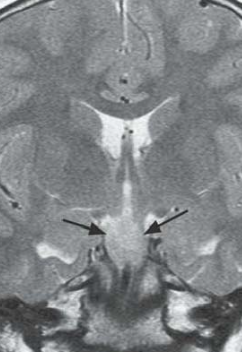

Tuber cinereum hamartoma

IRM

- Masse du tuber cinereum (entre corps mamillaires et tige pituitaire)

- IsoT1, Iso T2

- Pas de prise de contraste Gd+